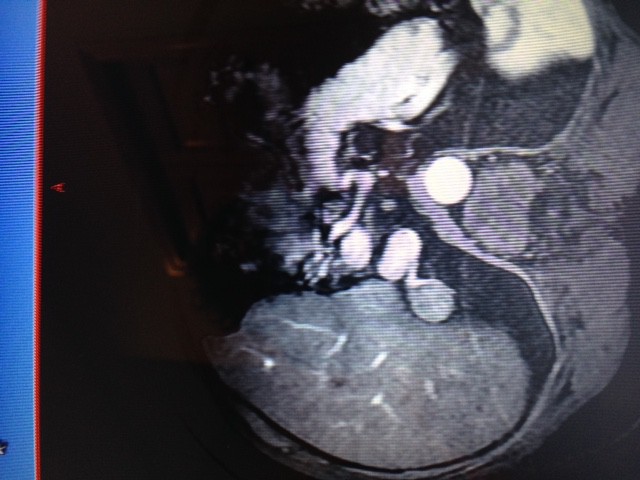

Can you see the HCC in segment 5, it has the vein growing to it and around it, it's encapsulated?? That's the one they are going after again. This pic is before the first attempt.RC